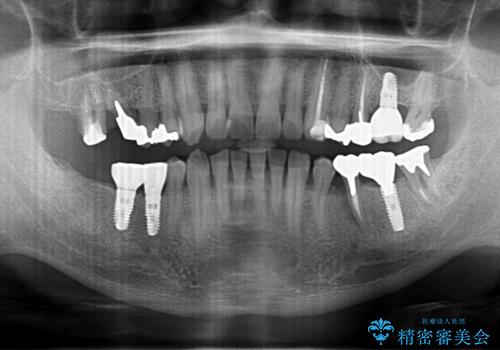

- 他院で奥歯が割れている為抜歯が必要と言われたとのことで来院。

右上56および左下5は割れていたためやむなく抜歯しインプラントにしていきました。

左下7(一番奥の歯)は抜歯をせずに済みましたが、高さがないため上の歯を矯正治療で沈め、また、歯ぐきの手術を合わせて行いクラウン(被せ物)をしっかり入れる処置をおこなっています。

治療後は、歯が割れないようにナイトガードをお渡ししています。